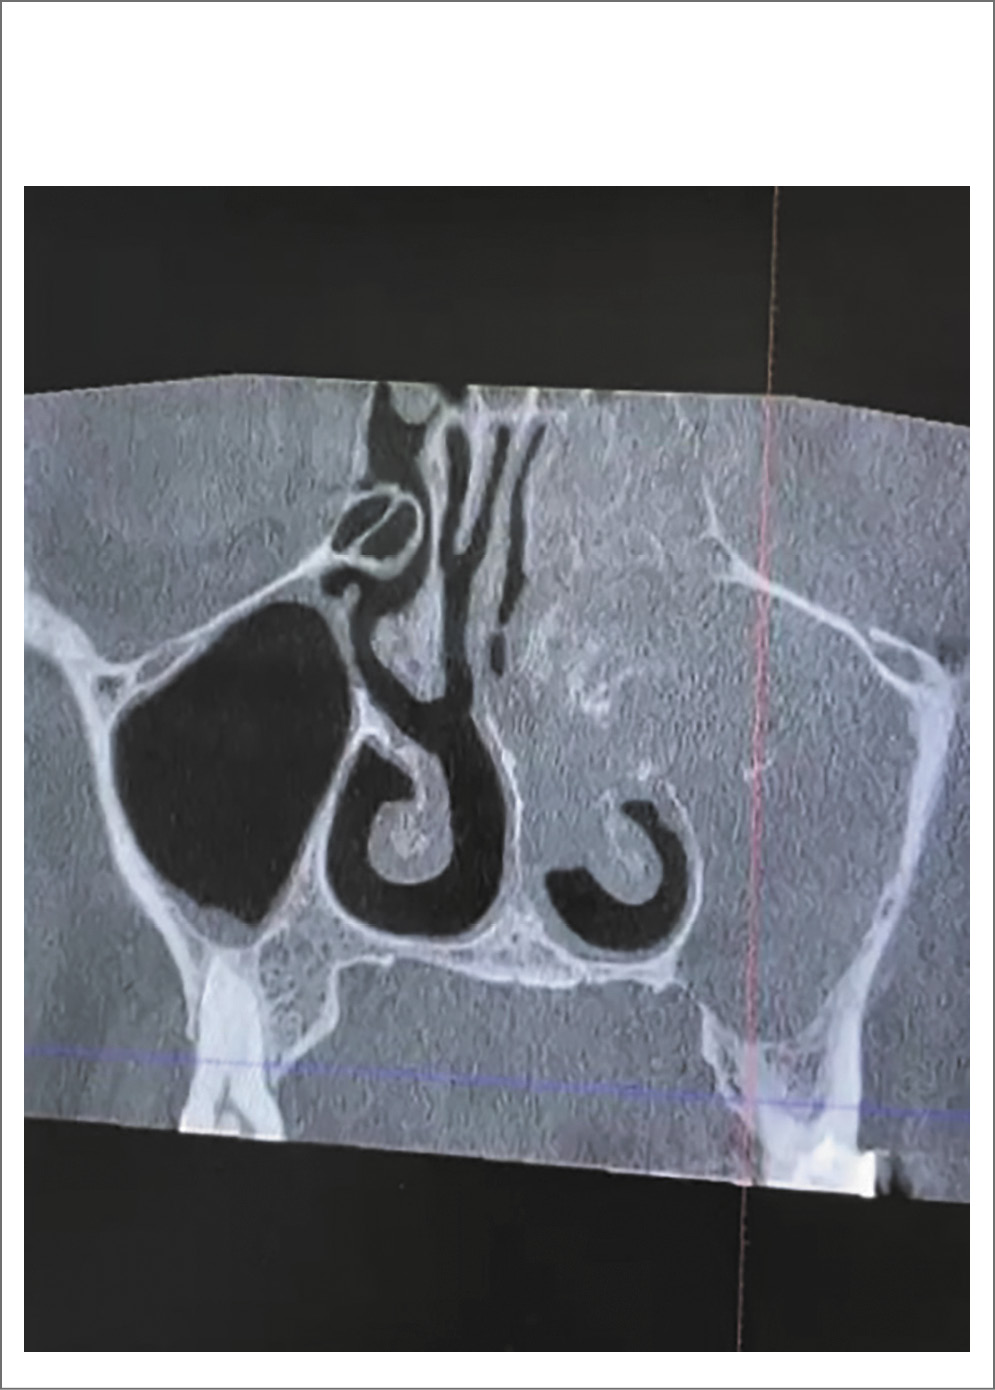

Из анамнеза, начало заболевания связывает с посещением частной стоматологической клиники летом (июль) 2021 г., где проходила лечение, в ходе которого проведена ревизия корней и каналов с пломбированием 2-го премоляра с последующим удалением через 1 мес 1-го моляра верхней челюсти слева. При повторном посещении стоматолога с указанными выше жалобами в начале октября врач клиники констатировал состоятельность пломбированного премоляра, отсутствие свища на месте удаленного зуба, была рекомендована консультация оториноларинголога. После проведения обычной рентгенографии ОНП и оториноларингологического осмотра выставлен диагноз: ПРС на фоне аллергического ринита. Прошла 2 курса лечения с использованием топической глюкокортикостероидной, противовоспалительной, антигистаминной, элиминационной терапии. Дважды короткими курсами (7 дней) принимала преднизолон – дозировки не помнит. Состояние не улучшилось. В июне 2022 г. после очередного посещения ЛОР-врача по месту жительства и проведения КТ носа и ОНП без контраста выставлен предварительный диагноз: новообразование левой ВП. Больная направлена на консультацию к онкологу (рис. 1).

Рис. 1. Массивное образование с деструкцией медиальной стенки ВП и клеток решетчатого лабиринта слева, смещение носовой перегородки.

После эндоскопической визуализации полости носа и регистрации слева полипозных вегетаций с характерной окраской и консистенцией, обильным выделением густого слизистого секрета (рис. 2) и предыдущей КТ носа и ОНП пациентке выполнена МСКТ с контрастным усилением, заключение: тотальное затемнение левой гайморовой пазухи, клеток решетчатого лабиринта с разрушением медиальной стенки ВП и проникновением в полости носа, смещение носовой перегородки и компрессия средней носовой раковины, наличие группы гиперденсивных включений округлой формы, контраст не накапливается (рис. 3). После выставления диагноза левостороннего хронического ПРС, мицетомы гайморовой пазухи и проведения соответствующей предоперационной подготовки пациентке выполнена гайморотомия по Колдуэлл–Люку, этмоидотомия слева. Отмечено в левой ВП наличие органических субстратов высокой плотности. Интраоперационно взятые подозрительные фрагменты поврежденных тканей направлены на гистологическое исследование с соответствующим диагнозом (рис. 4).

Рис. 3. Контрастное усиление. Аксиальная проекция.